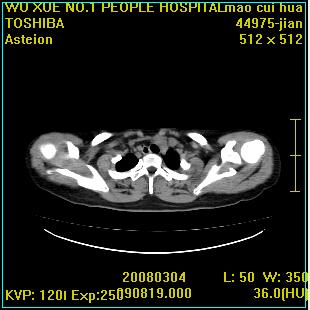

标题: CT12025:男,50岁,左肩活动受限半年。

肩关节骨质破坏呈小囊状,其周软组织轻度肿胀,余未见异常。

考虑:肩袖损伤。建议mri。

左侧肱骨头密度不均匀,高低混杂,周围软组织略肿胀,考虑结核性病变。

左侧肱骨头密度不均匀,高低混杂,髓腔密度稍高,周围软组织略肿胀,肌间隙模糊,考虑慢性骨髓炎可能。密切结合临床!